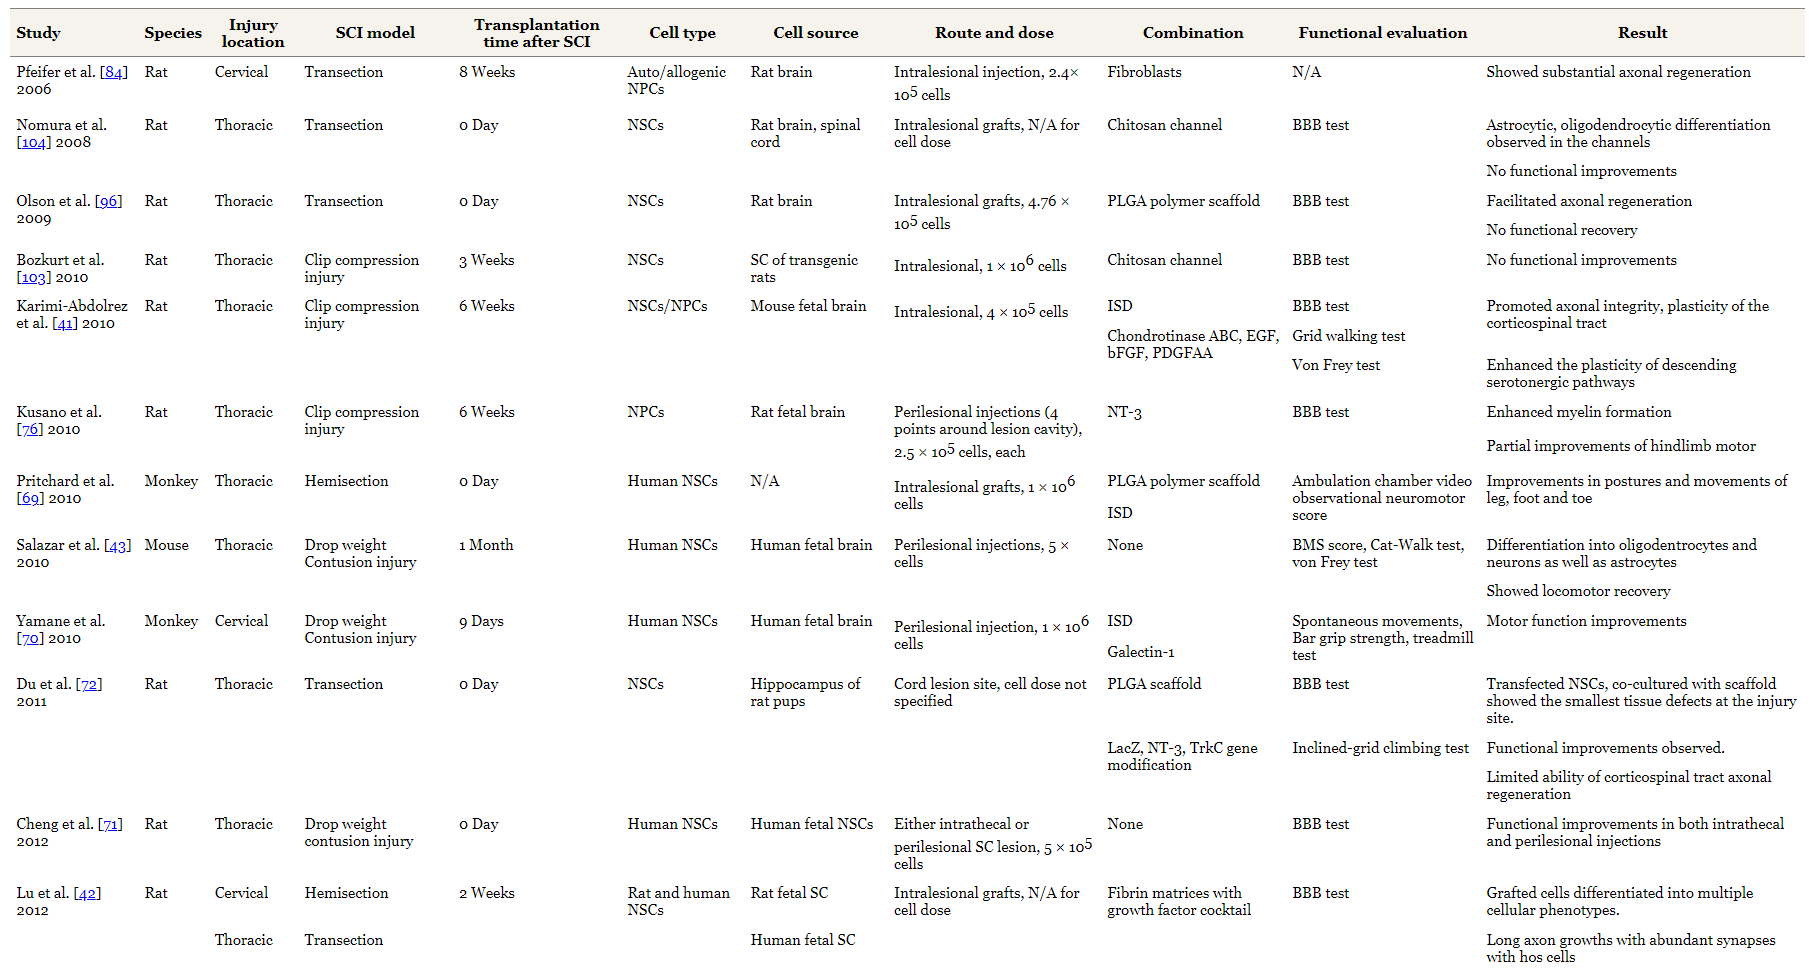

表1總結(jié)了使用NSC的實驗研究的特點。NSC治療已在SCI的各個階段進(jìn)行了測試:急性、亞急性和慢性。小鼠和大鼠是最常用的動物。

如表1所示,大多數(shù)使用NSC的臨床前研究均采用椎管內(nèi)途徑進(jìn)行細(xì)胞移植。雨森等人比較了急性挫傷性 SCI模型中的鞘內(nèi)和椎管內(nèi)給藥途徑。這兩種方法都有利于功能性運動恢復(fù)。然而,椎管內(nèi)注射組病變處的細(xì)胞移植物存活率更好,他們得出結(jié)論,椎管內(nèi)移植對長期脊髓組織再生更有幫助。

參考表1,大多數(shù)臨床前研究NSC已使用大約5×105至1×106個細(xì)胞進(jìn)行椎管內(nèi)細(xì)胞移植。尤瑟菲法德等人表明較高的細(xì)胞劑量(>3×106個細(xì)胞/kg)是移植的最佳選擇。然而,少數(shù)研究表明,移植的干細(xì)胞存活數(shù)量存在一定閾值,移植細(xì)胞數(shù)量與功能恢復(fù)之間不存在相關(guān)性。需要進(jìn)一步的研究來確定移植細(xì)胞數(shù)量的最佳范圍,不僅在動物模型中,而且在人類中。